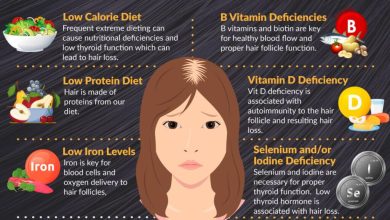

महिलाओं का शरीर जीवनभर कई तरह के हार्मोनल बदलावों से गुजरता है- कभी उम्र के साथ आने वाले बदलाव, कभी प्रेग्नेंसी, तो कभी सेहत से जुड़ी किसी समस्या के कारण। इन बदलावों का असर सिर्फ मूड या एनर्जी पर ही नहीं होता, बल्कि शरीर के ब्लड शुगर को नियंत्रित करने की क्षमता पर भी गहरा प्रभाव डालता है।

PCOS यानी पॉलीसिस्टिक ओवरी सिंड्रोम केवल पीरियड्स या फर्टिलिटी से जुड़ी समस्या नहीं है। इससे शरीर में इंसुलिन के प्रति संवेदनशीलता कम हो सकती है, जिसे इंसुलिन रेजिस्टेंस कहते हैं। ऐसी स्थिति में शरीर को शुगर को एनर्जी में बदलने के लिए ज्यादा इंसुलिन की जरूरत पड़ती है।

धीरे-धीरे यह असंतुलन आगे चलकर डायबिटीज का खतरा बढ़ा सकता है। इसलिए PCOS को एक ऐसे संकेत के रूप में समझना जरूरी है जो महिला की लंबी अवधि की मेटाबॉलिक सेहत को प्रभावित कर सकता है।

प्रेग्नेंसी में शरीर में होने वाले बदलाव सामान्य दिनों की तुलना में अलग तरह की जरूरतें पैदा करते हैं। इस दौरान इंसुलिन की मांग बढ़ जाती है। अगर शरीर इस अतिरिक्त मांग को पूरा नहीं कर पाता, तो जेस्टेशनल डायबिटीज विकसित हो सकती है।

मेनोपॉज की अवस्था में एस्ट्रोजन का स्तर धीरे-धीरे कम होने लगता है। यह हार्मोन शरीर को इंसुलिन के प्रति अधिक संवेदनशील बनाता है। जब इसका स्तर गिरता है, तो:

वजन तेजी से बढ़ सकता है

शुगर लेवल अचानक ऊपर-नीचे हो सकता है

शरीर की ऊर्जा और मेटाबॉलिज्म धीमे पड़ सकते हैं

यह सब मिलकर ब्लड ग्लूकोज नियंत्रण को कठिन बना देता है और डायबिटीज का खतरा बढ़ जाता है।